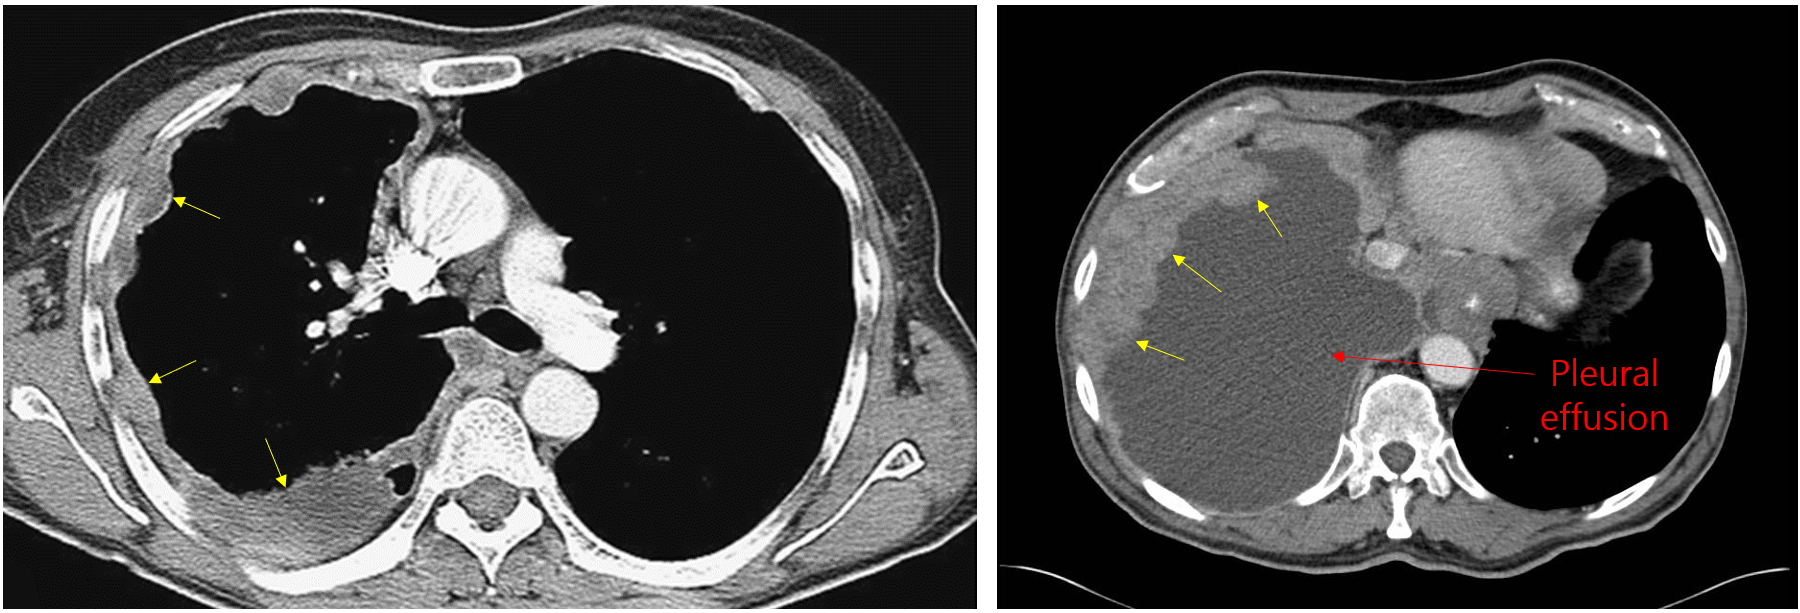

(2) CXR/CT

① 단순 규폐증: 폐 상부~중부의 small, rounded nodules (< 10 mm)

• Hilar LN 주변에 calcification 있을 수 있음 (egg-shell calcification)

② PMF: Nodule들이 서로 융합하며 불규칙한 덩이 형성 (≥ 10 mm)

(1) CXR/CT

① 석면폐증: 폐하부 diffuse GGO, sagging heart, reticular opacities, subpleural line 등

② 흉막판: Pleura의 국소적 thickening, calcification. 석면 노출을 강력히 시사

③ 악성 흉막중피종: 두꺼워진 pleural mass